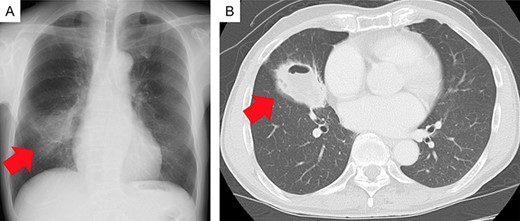

Chest radiography revealed an abnormal shadow in the right-middle lung field (Fig. 1A). Chest computed tomography (CT) revealed a tumor with a cavity, ~55 mm in diameter, in the right-middle lobe (Fig. 1B). The tumor was diagnosed as a lung squamous cell carcinoma by transbronchial biopsy.

Imaging findings. (A) Chest radiograph showing an abnormal shadow in the right-middle lung field (red arrow). (B) Chest computed tomography scan showing a tumor with a cavity, ~55 mm in diameter, in the right-middle lobe (red arrow).